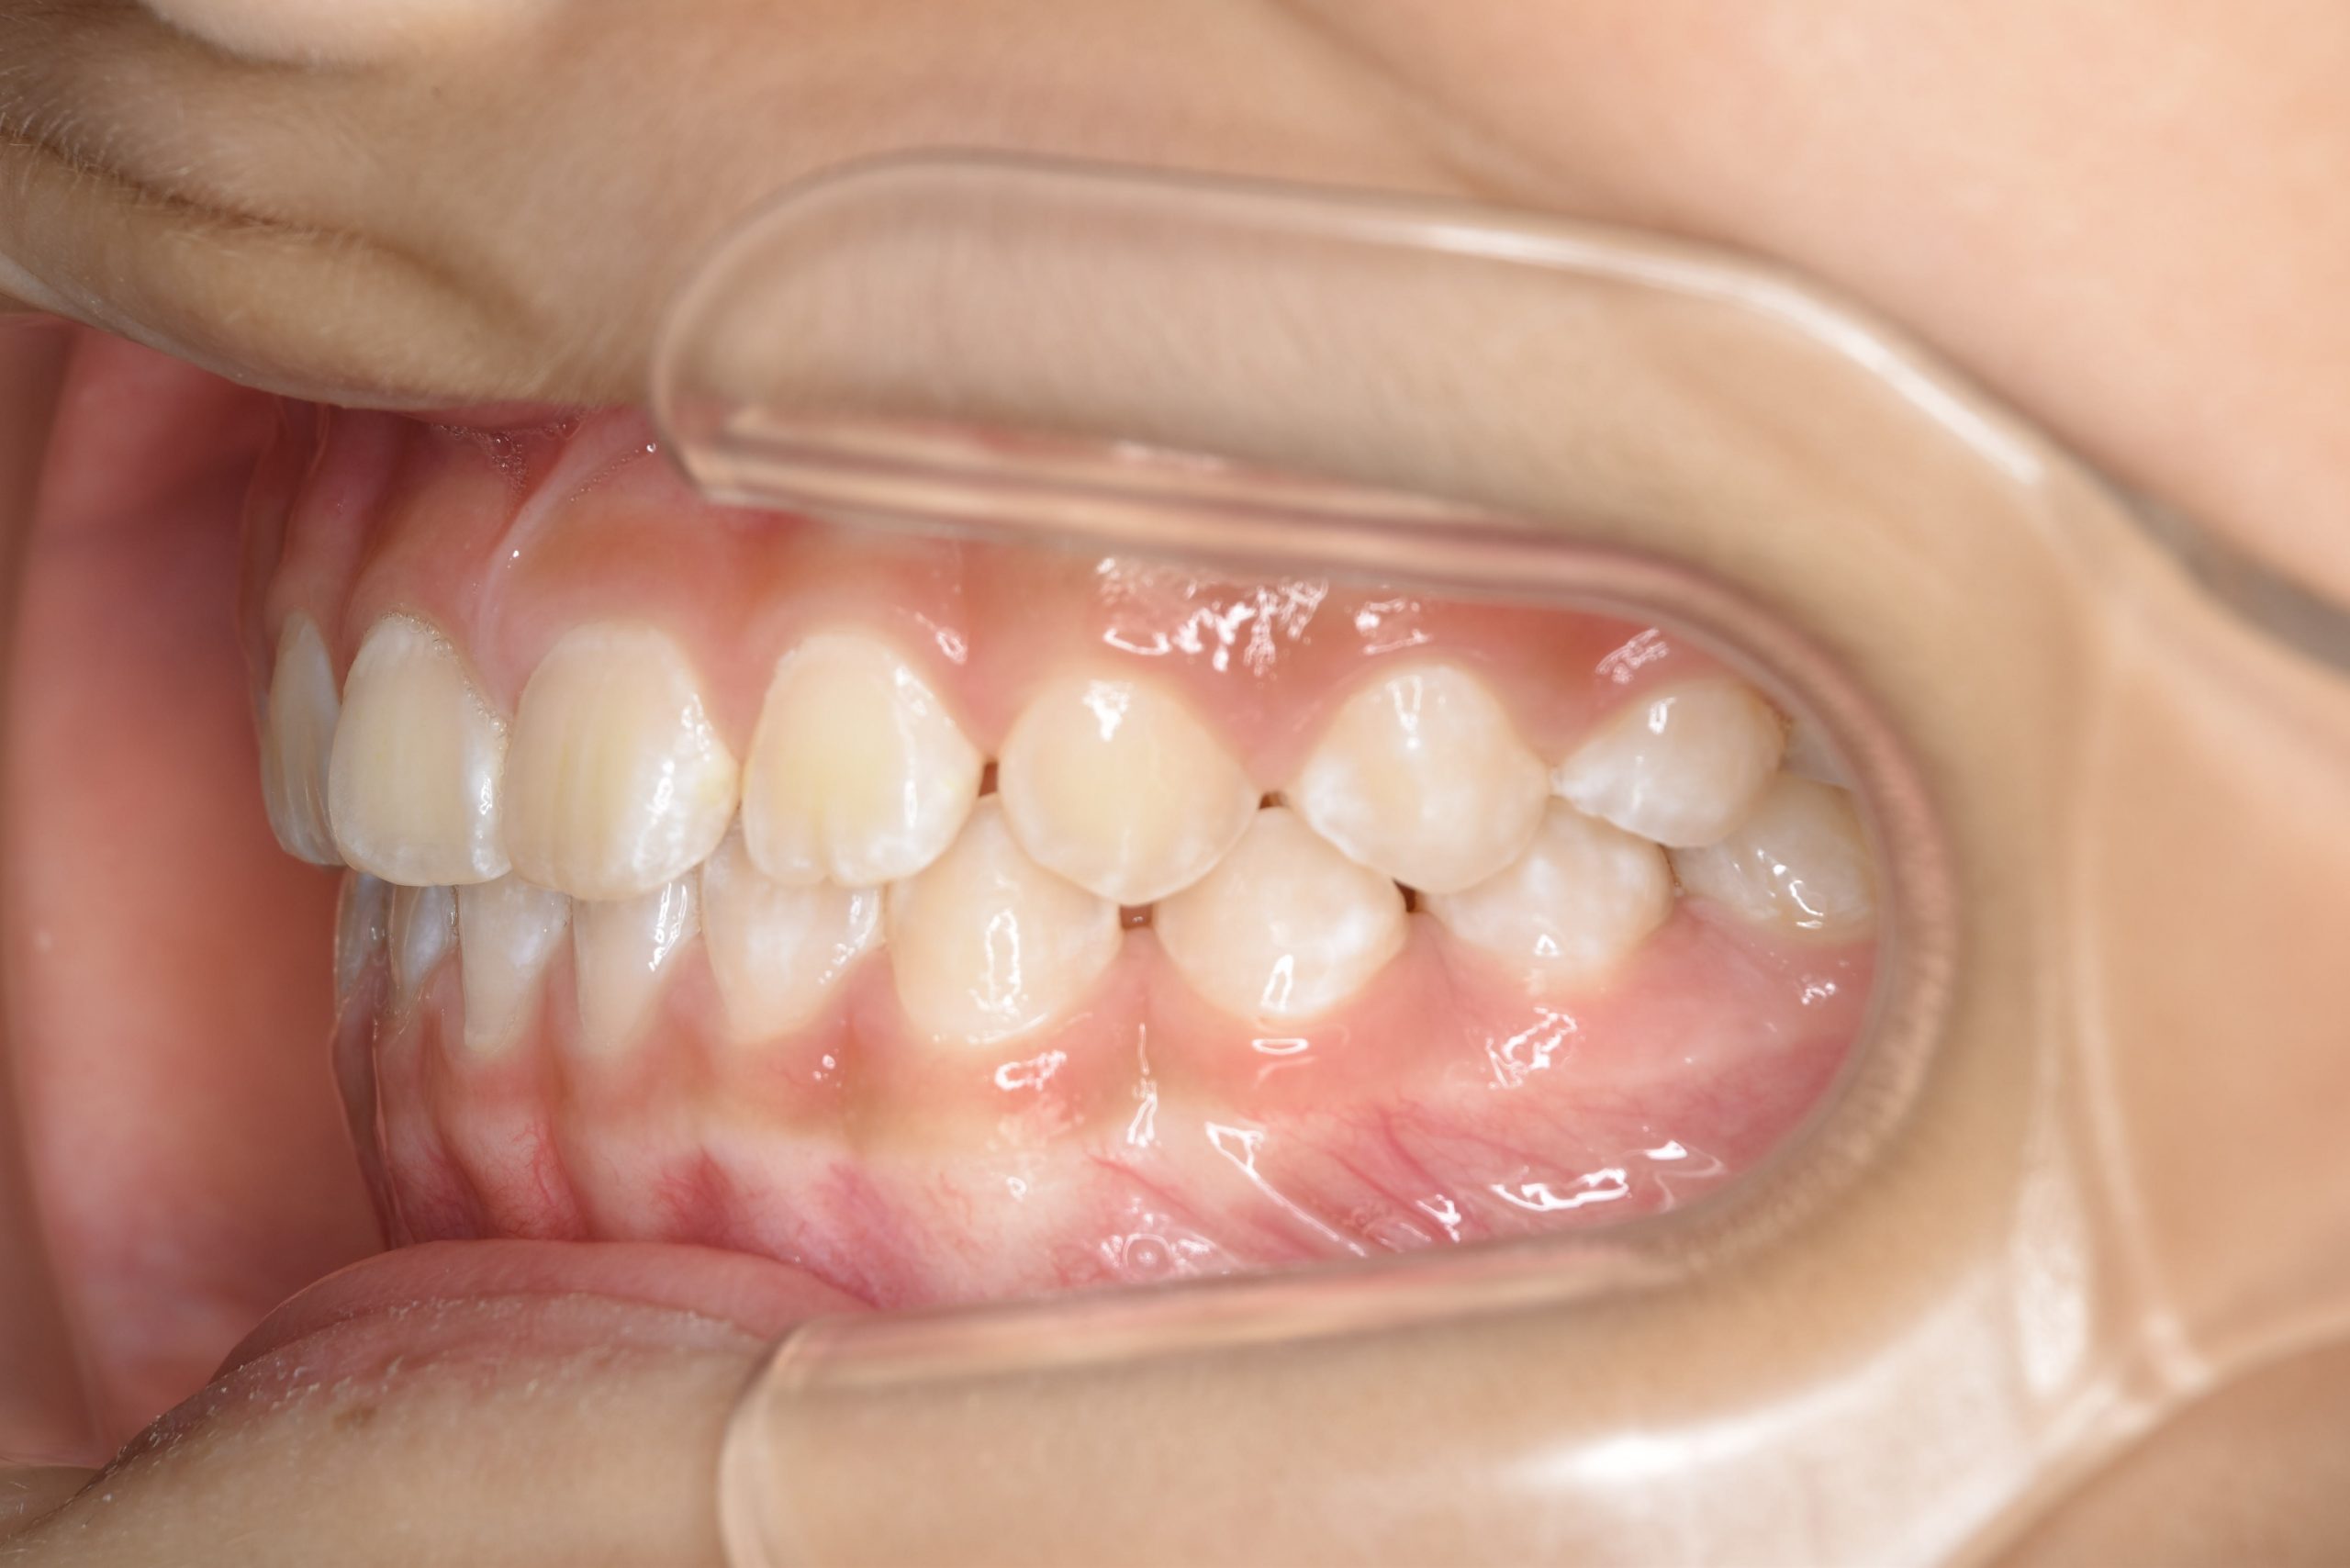

アフター

主訴 下顎が出ている

施術内容 上顎急速拡大装置と下顎リンガルアーチを用いて上下顎骨を拡大した。

上顎前方牽引装置を用いて上顎骨を前方に成長促進させた。

その後マウスピース型矯正装置で歯牙を配列し良好な咬合を獲得した。

治癒期間 1年6か月 ※経過観察含む